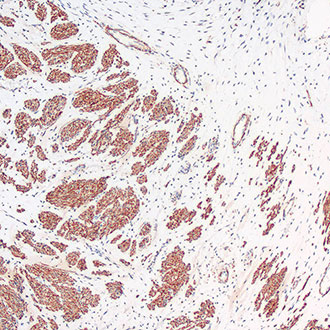

IHC

免疫组织化学(IHC)